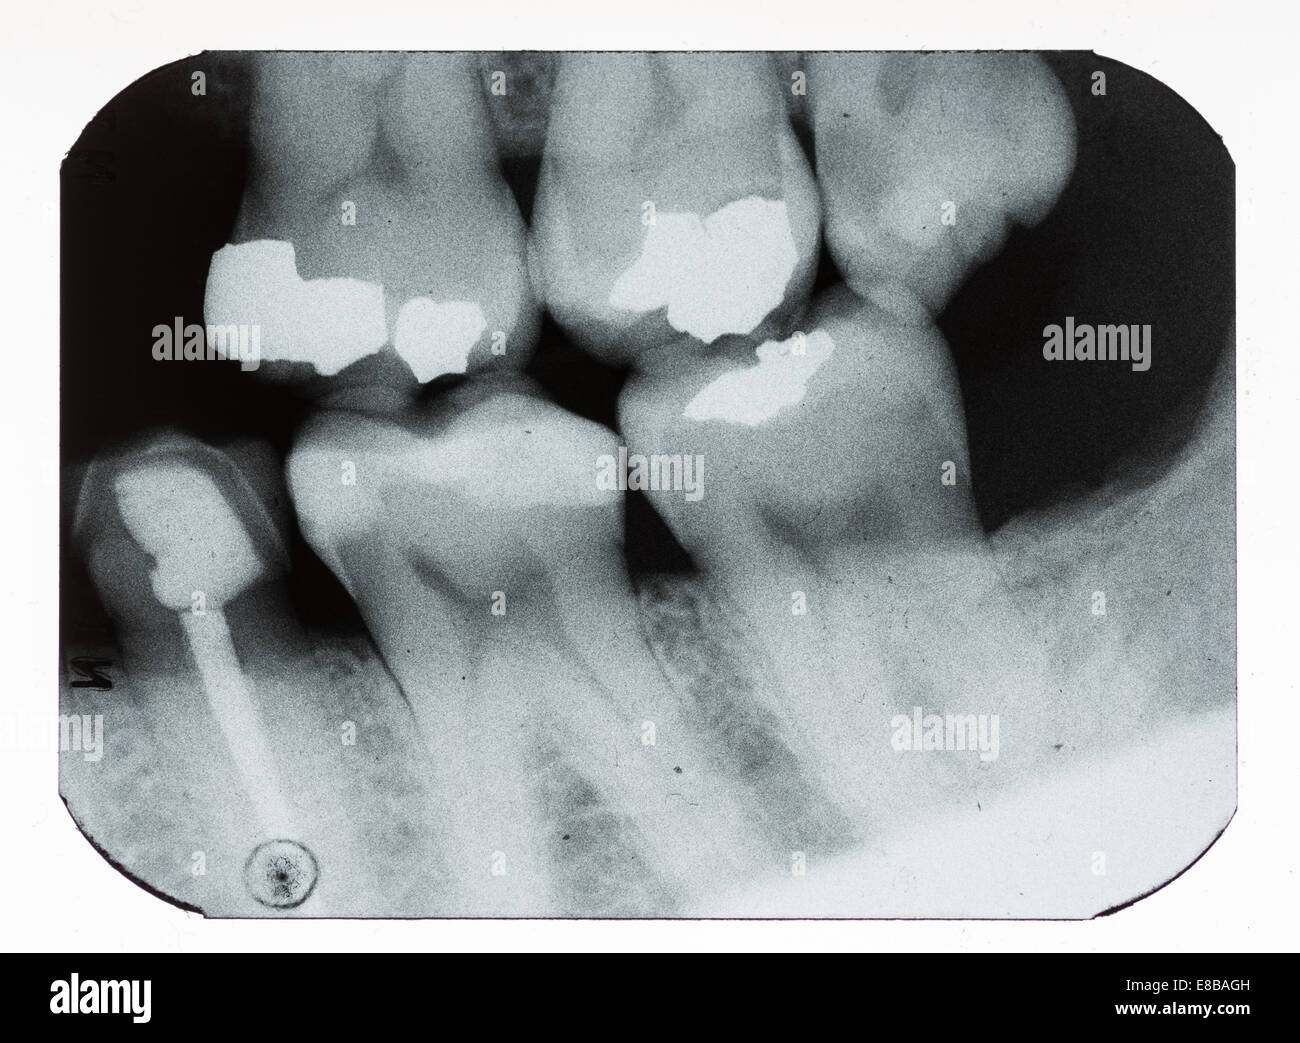

dental xray showing fillings and missing teeth Stock Photo Alamy X Ray Of Tooth With Filling Here is a picture of what a different tooth with decay underneath of an existing filling looks like. Your honest dentist will try to save the tooth for you with either a filling, crown, or. There is no real explanation for it usually. They are able to diagnose issues like cavities early and fix them quickly, helping patients avoid unnecessary. X Ray Of Tooth With Filling.

Dental Xray Showing Fillings Photograph by Gjlp Cnri Pixels X Ray Of Tooth With Filling Dental cavities are one of the most common worldwide dental problems, affecting millions yearly. They are able to diagnose issues like cavities early and fix them quickly, helping patients avoid unnecessary pain, cost, and further damage. For example, under a filling, or between the teeth. Here is a picture of what a different tooth with decay underneath of an existing. X Ray Of Tooth With Filling.